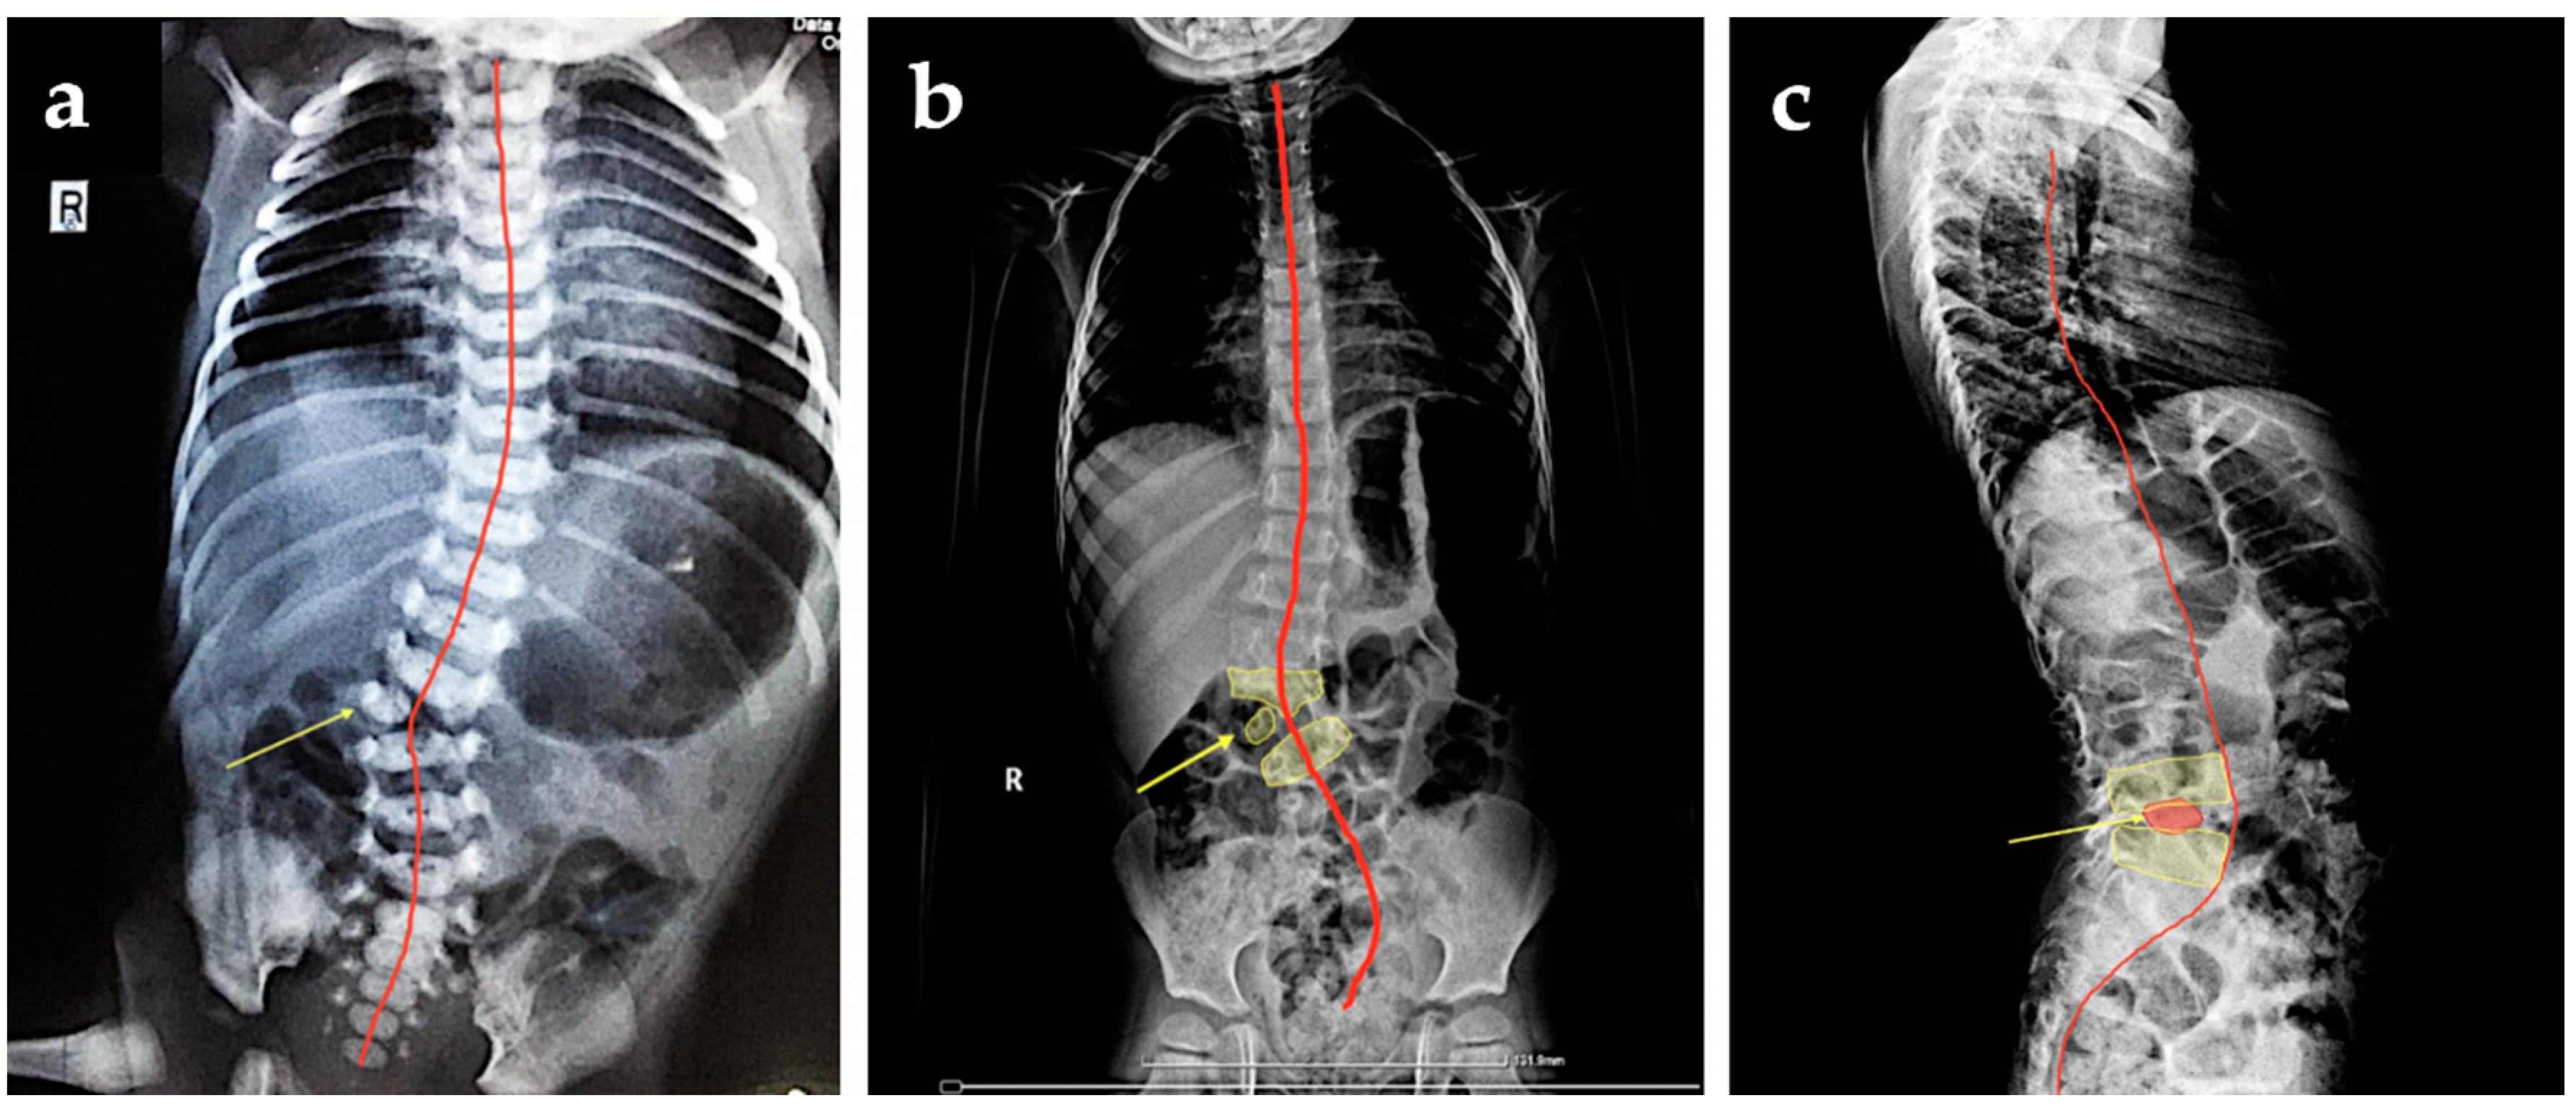

X-ray postnatal evaluation confirmed the early prenatal ultrasonographic diagnosis (Figure 3a). The parents refused further complementary imaging (MRI) despite the medical advice. The X-ray performed in the current year revealed in the anterior-posterior face X-ray of the thoracolumbar child’s spine, the hemivertebra, along with a mild scoliosis (Figure 3b,c).

Figure 3.

X-ray findings: (a) anteroposterior face of the child’s spine at 8 months after delivery indicating hemivertebra (yellow arrow); (b) anteroposterior X-ray face of the patient spine at 4-years-old depicting hemivertebra (yellow arrow) and scoliosis (red line), (c) lateral profile of the spine focused on the thoracolumbar section revealed the hemivertebra (yellow arrow), and curvature of the spine (red line).